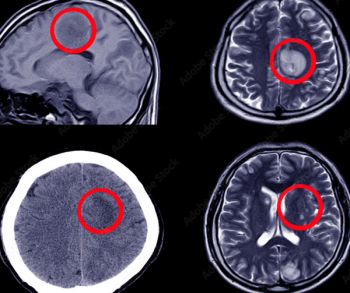

What is your diagnosis?